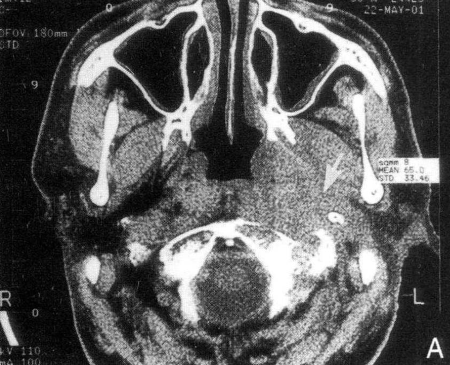

Sebagian besar kasus kanker nasofaring memiliki respons yang cukup baik terhadap radioterapi, sehingga terapi radiasi menjadi pilihan utama dalam pengobatannya. Namun, pada kasus dengan tingkat diferensiasi sel yang buruk, stadium lanjut, atau bila terjadi kekambuhan setelah radioterapi, kombinasi dengan pembedahan dan kemoterapi juga menjadi bagian penting dari pendekatan pengobatan yang tidak boleh diabaikan.

Pasien kanker nasofaring umumnya dapat menjalani radioterapi, kecuali bila terdapat kontraindikasi yang jelas. Jenis radioterapi baik bersifat kuratif maupun paliatif akan disesuaikan dengan kondisi masing-masing pasien. Radioterapi kuratif bertujuan untuk menyembuhkan, sementara radioterapi paliatif difokuskan untuk mengurangi nyeri, meredakan gejala, dan memperpanjang harapan hidup pada pasien dengan stadium lanjut. Untuk pasien yang baru pertama kali menjalani pengobatan (kasus awal) dan belum mengalami penyebaran (metastasis), biasanya dianjurkan menjalani radioterapi kuratif atau kombinasi radioterapi dengan kemoterapi. Jika sejak awal sudah terdapat metastasis ke organ lain, maka pengobatan umumnya dimulai dengan kemoterapi untuk mengendalikan penyebaran, dan radioterapi lokal dapat dipertimbangkan jika respons terhadap kemoterapi baik. Pada pasien yang mengalami kekambuhan lokal setelah menjalani radioterapi, radioterapi ulang (tahap kedua) dapat diberikan, namun umumnya hanya dipertimbangkan jika sudah lebih dari satu tahun sejak terapi pertama. Sementara itu, jika pasien mengalami nyeri tulang atau gejala lokal akibat metastasis jauh yang tidak merespons kemoterapi, maka radioterapi paliatif lokal pada area yang terkena dapat menjadi pilihan untuk meredakan gejala.

Indikasi meliputi: pasien dengan lesi terbatas di nasofaring yang tidak menghilang atau mengalami kekambuhan setelah radioterapi. Jika terdapat benjolan tunggal berupa pembesaran kelenjar getah bening di leher yang tetap aktif dan tidak mengecil setelah radioterapi—sementara tumor primer di nasofaring sudah terkendali—maka dapat dipertimbangkan tindakan pembedahan berupa diseksi kelenjar getah bening.